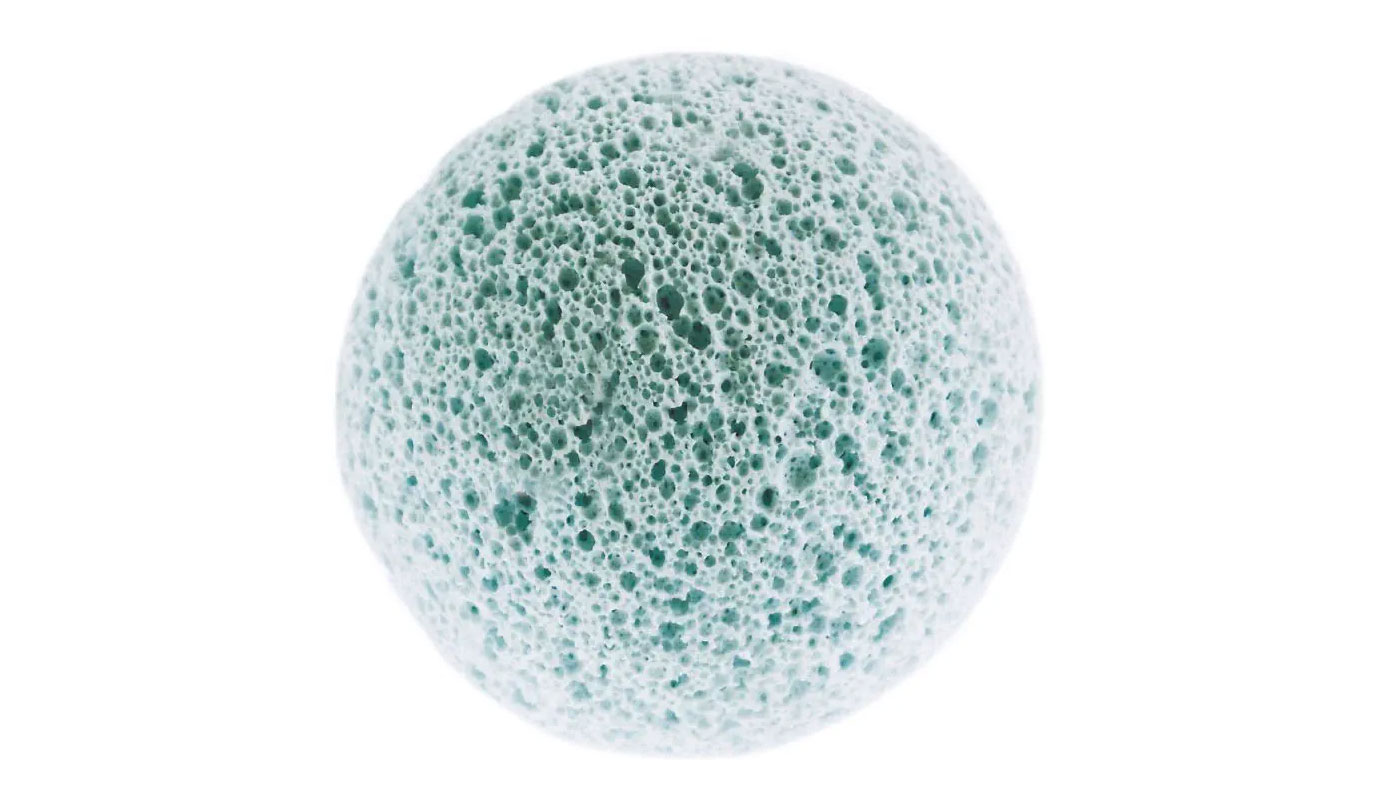

- 義眼台

- 2つ目は、義眼台としてのアクリルやハイドロキシアパタイトなどの生体親和性のある人工物です。ヒアルロン酸とは異なり、義眼台自体にそれなりの体積がありますので、一度入れれば、それだけでそれなりの容積を確保することが可能になります。

義眼台により、

義眼は約半分の薄さに

眼球の体積は約7㏄です。

これが喪失したとしてすべてを義眼で補うなら義眼の体積は5-6㏄程度は必要ですが、直径18ミリの義眼台では3.1㏄、直径20ミリの義眼台では4.2㏄の体積がありますから、これらの義眼台を入れられれば、義眼の体積は2-3㏄で良いことになり、約半分の薄さにすることが可能なのです。

当院では、生体親和性の高い義眼台を使用しています

こういった事情に対応するため、当院では海外で認可された義眼台を輸入し眼窩に包埋する手術をしていますし、いままで同様アクリルなどの素材を使ったボールも挿入しています。

海外で使われている義眼台は、アクリルボールと異なり、細かい穴が開いているため眼窩の組織に生着しやすく、ばい菌による感染にも強いとされていますが、実績を見ると成績にはほとんど差がないようです。